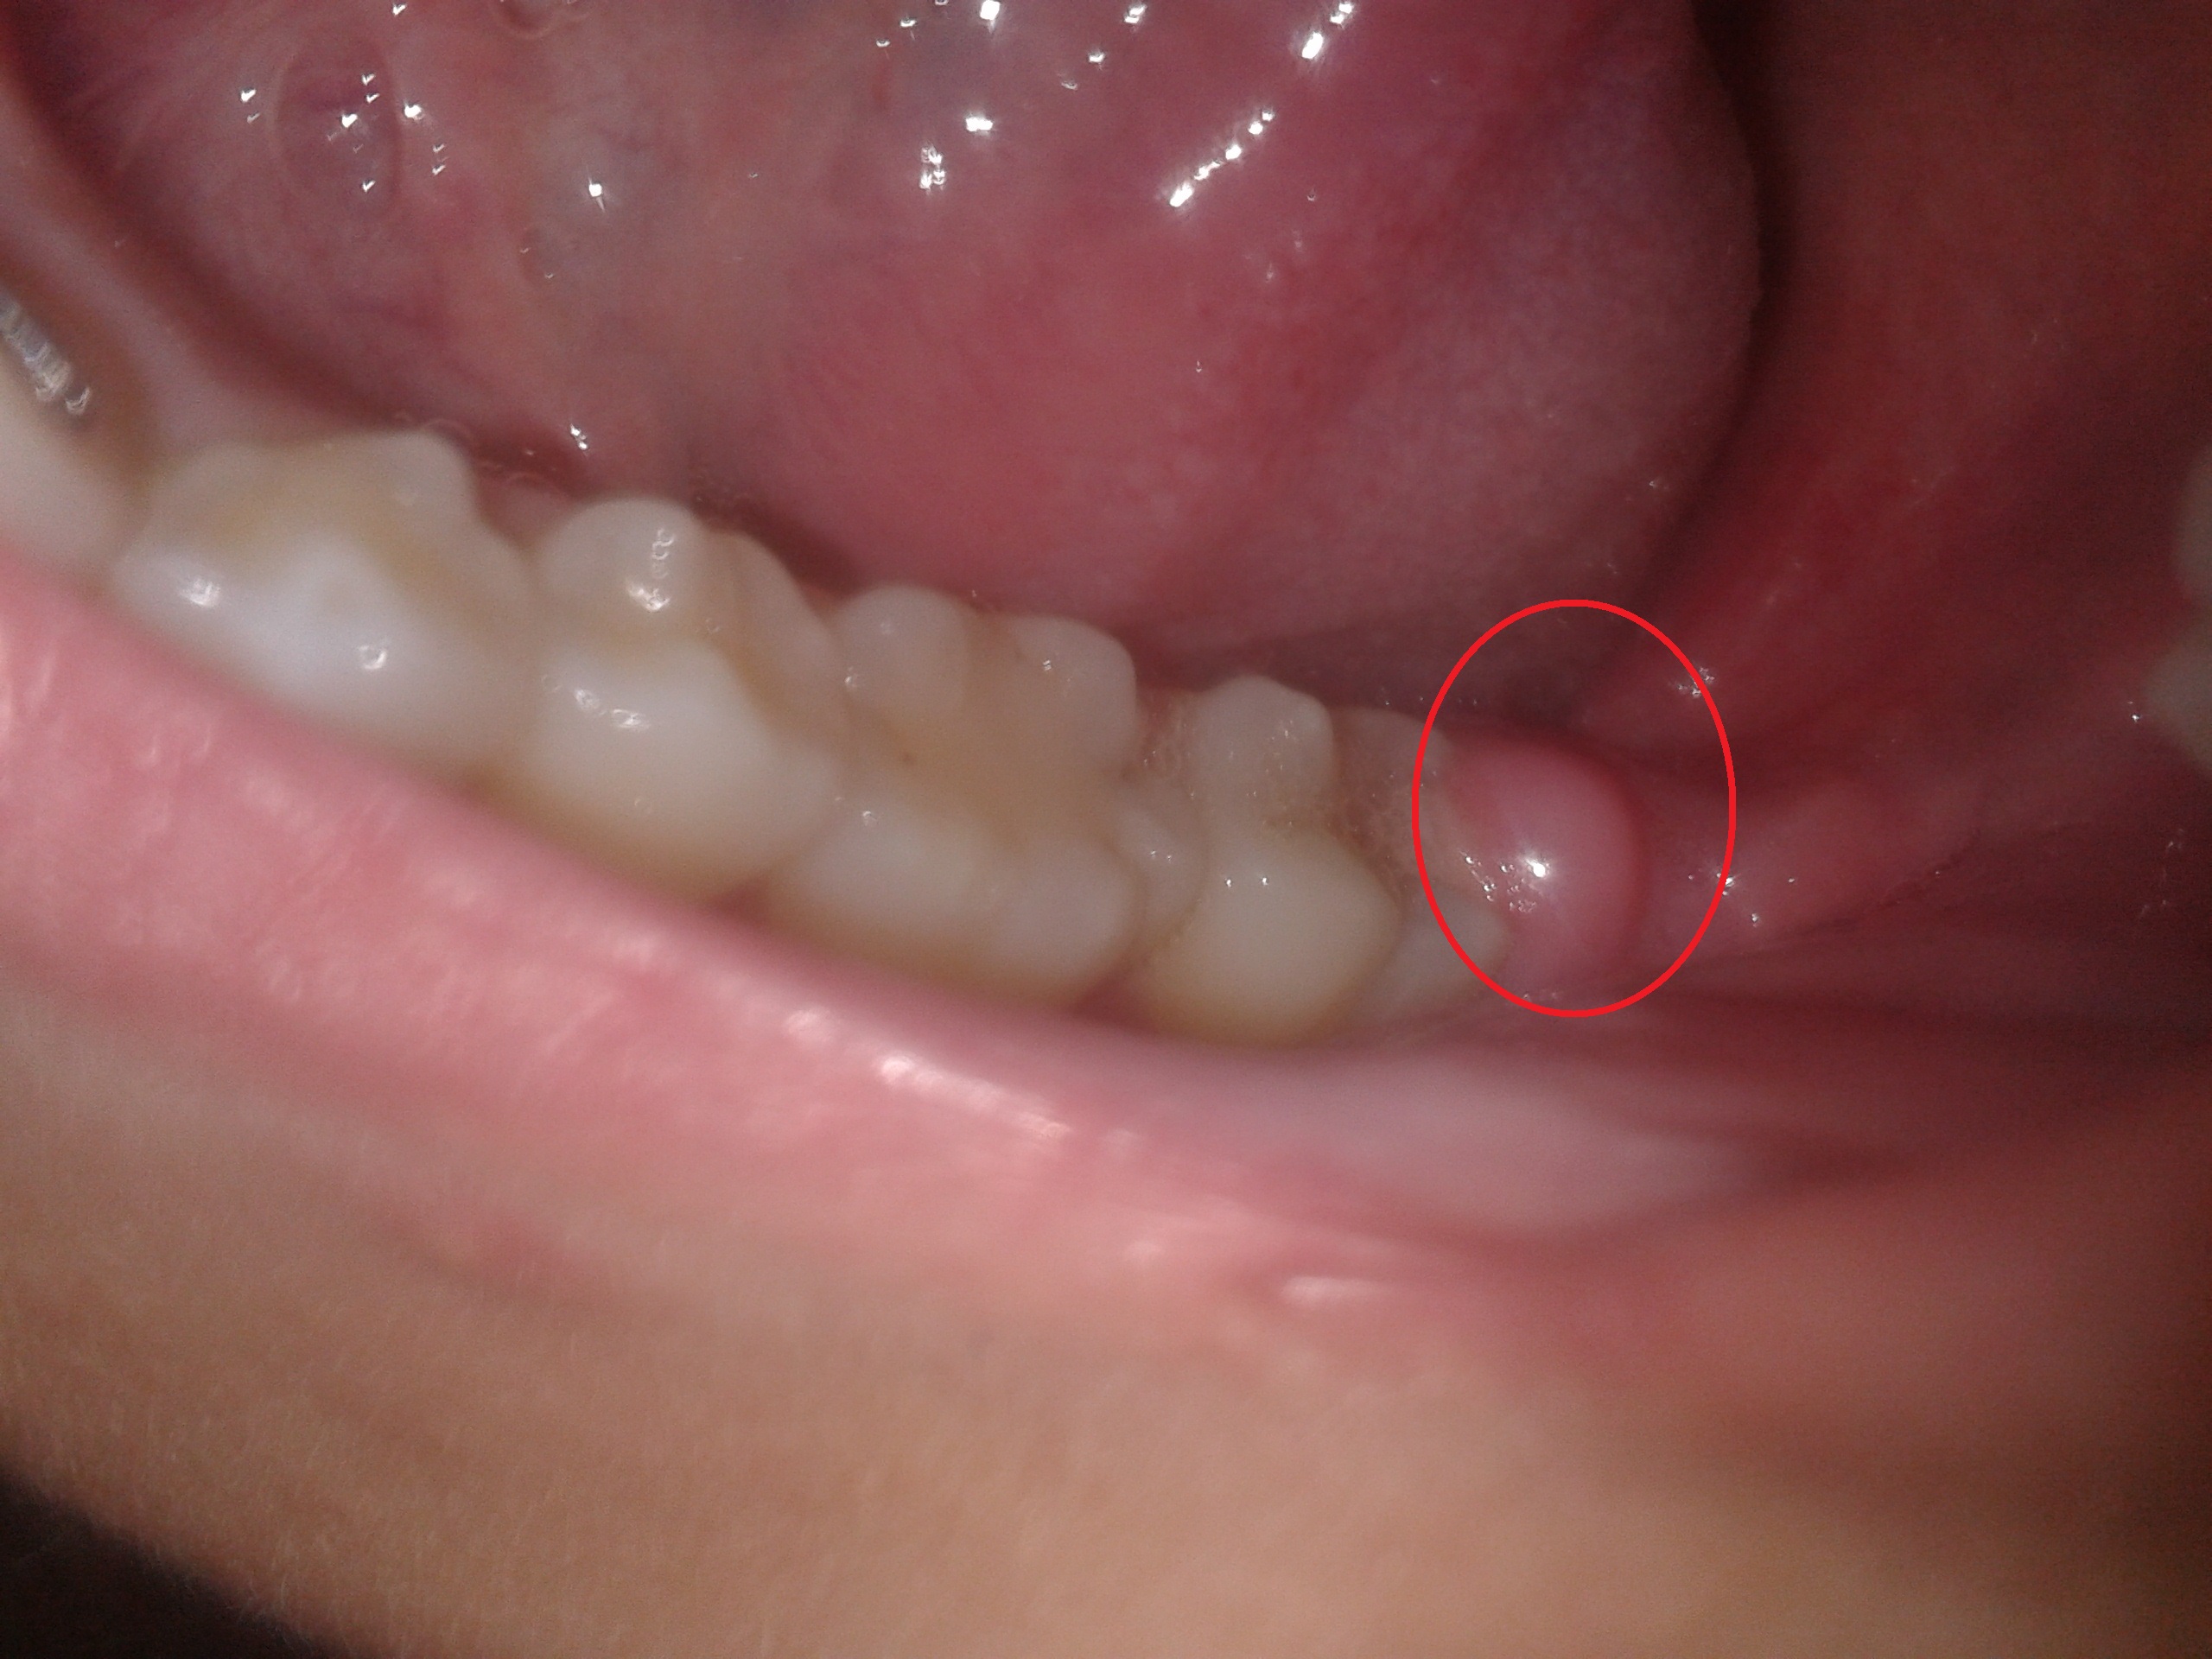

Boule Sur La Gencive Cmd Balexert

Enflure Ou Bosse Sur La Gencive Bucco